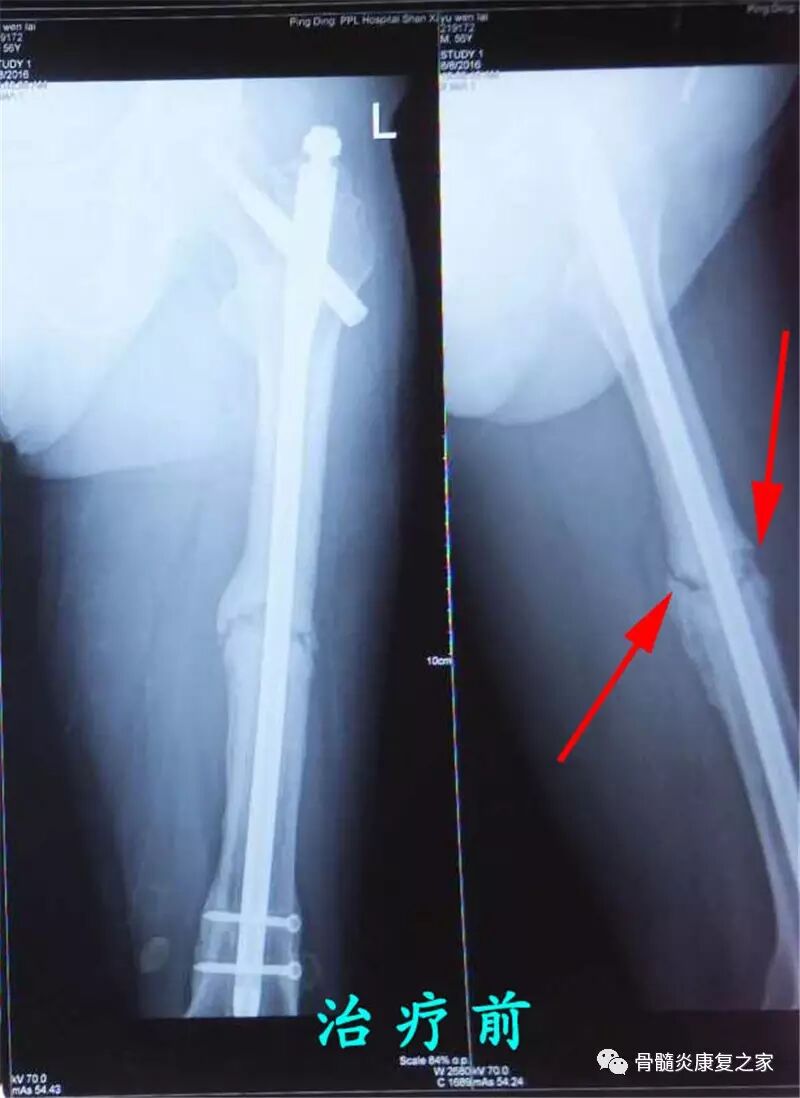

病史简介: 患者于2014年6月份车祸至左股骨粉碎性骨折及左股骨粗隆间骨折,到阳泉阳煤集团医院就诊,给予手术及内固定处理,住院15天,回家疗养。2015年5月份到阳煤集团医院给予冲击波治疗一月余,无好转。2015年10月份,到山西平定县医院就诊,给予手术及植骨治疗,住院15天,回家疗养。但骨折至今未愈合。2016年9月份,患者为求进一步诊治,故来我院就诊。

患者初入院时片子显示情况:骨折线清晰可见,没有骨痂生成

患者治疗四个月后拍片检查,片子显示:骨折线模糊,有骨痂生成,新生骨填充。